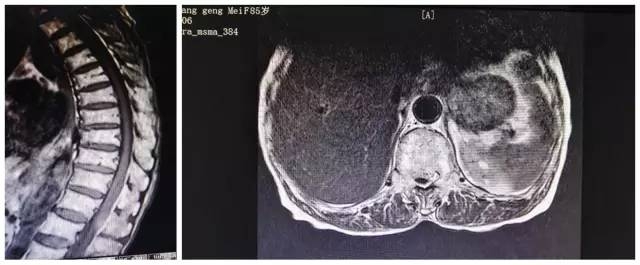

家人曾听说惠州市第三人民医院骨科医术精湛,为求进一步治疗,连夜把奶奶送往三院东院区科医学中心颈肩腰腿痛科,科室医师高度重视,发起骨科医学中心内部多专科联合诊疗机制,经于脊柱外科会诊并在院内相关部门协调下申请了急诊核磁共振等检查,结果显示“胸腰段椎管内占位(性质待查)”。中心主任武明鑫博士查看病人及各项资料后基本判定为“胸腰段的椎管内硬膜外出血导致瘫痪”。

病人MRl(核磁共振成像)检查片

由于椎管内占位压迫神经并已导致瘫痪,需尽早手术减压,不然可能会导致永久瘫痪,但因奶奶年纪大,麻醉等方面风险高,家属一度想放弃手术。武明鑫博士立即组织医生们进行了全面的术前讨论,制定周密的手术方案,要求椎管内占位病灶应尽快清除,解除脊髓压迫。

为了消除家属们的担忧,颈肩腰腿痛科许球祥主任及孙进医生为家属详细的解释了手术的必要性及风险性,表示达到预期效果,可以大大改善婆婆的生活质量,为家庭减少一份重担!最终家属们选择相信骨科团队,当天即予施行急诊减压清除血肿手术,手术历时约2小时,术中显示确实和术前判断一致,为“椎管内硬膜外出血”。术后第一天老人家大小便失禁的症状就消失了,双下肢肌力明显恢复,术后一周时下肢肌力也基本恢复正常。